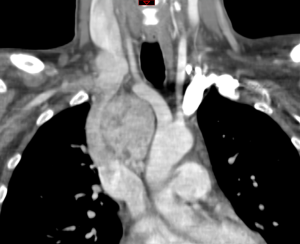

Herein we present here a case of SVCS caused by an ectopic thyroid lobe mimicking a mediastinal tumor. A 42-year-old woman went to our unit with facial flush and swelling and headache. Patient medical history was unremarkable, no smoking habits was remarked. During the neck examination a right lymphadenopathy was palpable and goiter thyroid was observed on the left side. An unclear mediastinal mass was observed at chest radiography associated with a tracheal compression (Figure 1). A Computed Tomography was performed (Figure 2). A scintigraphy was performed and a thyroid goiter was diagnosed. The patient underwent to surgical excision of the tumoral mass by sternotomy incision associating a thyroidectomy. Surgery was uneventful and patient was discharged on post operative day 7. Thyroid tissue was observed at pathology exam. Mediastinal ectopic thyroid tissue is rare. This finding is an embryological abnormality characterized by the occurrence of thyroid tissue in a site other than its usual location. The Ectopic tissues are currently described in literature and it is a result of a migration defect during embryological development or after a trauma (2,3). SVCS is in near of 97% of cases caused by malignancy (1) and thyroid cancer as primary etiology is extremely rare (4). In our case a secondary goiter of ectopic thyroid tissue was the cause of SVCS; surgical treatment was a therapeutic cure for the patient.